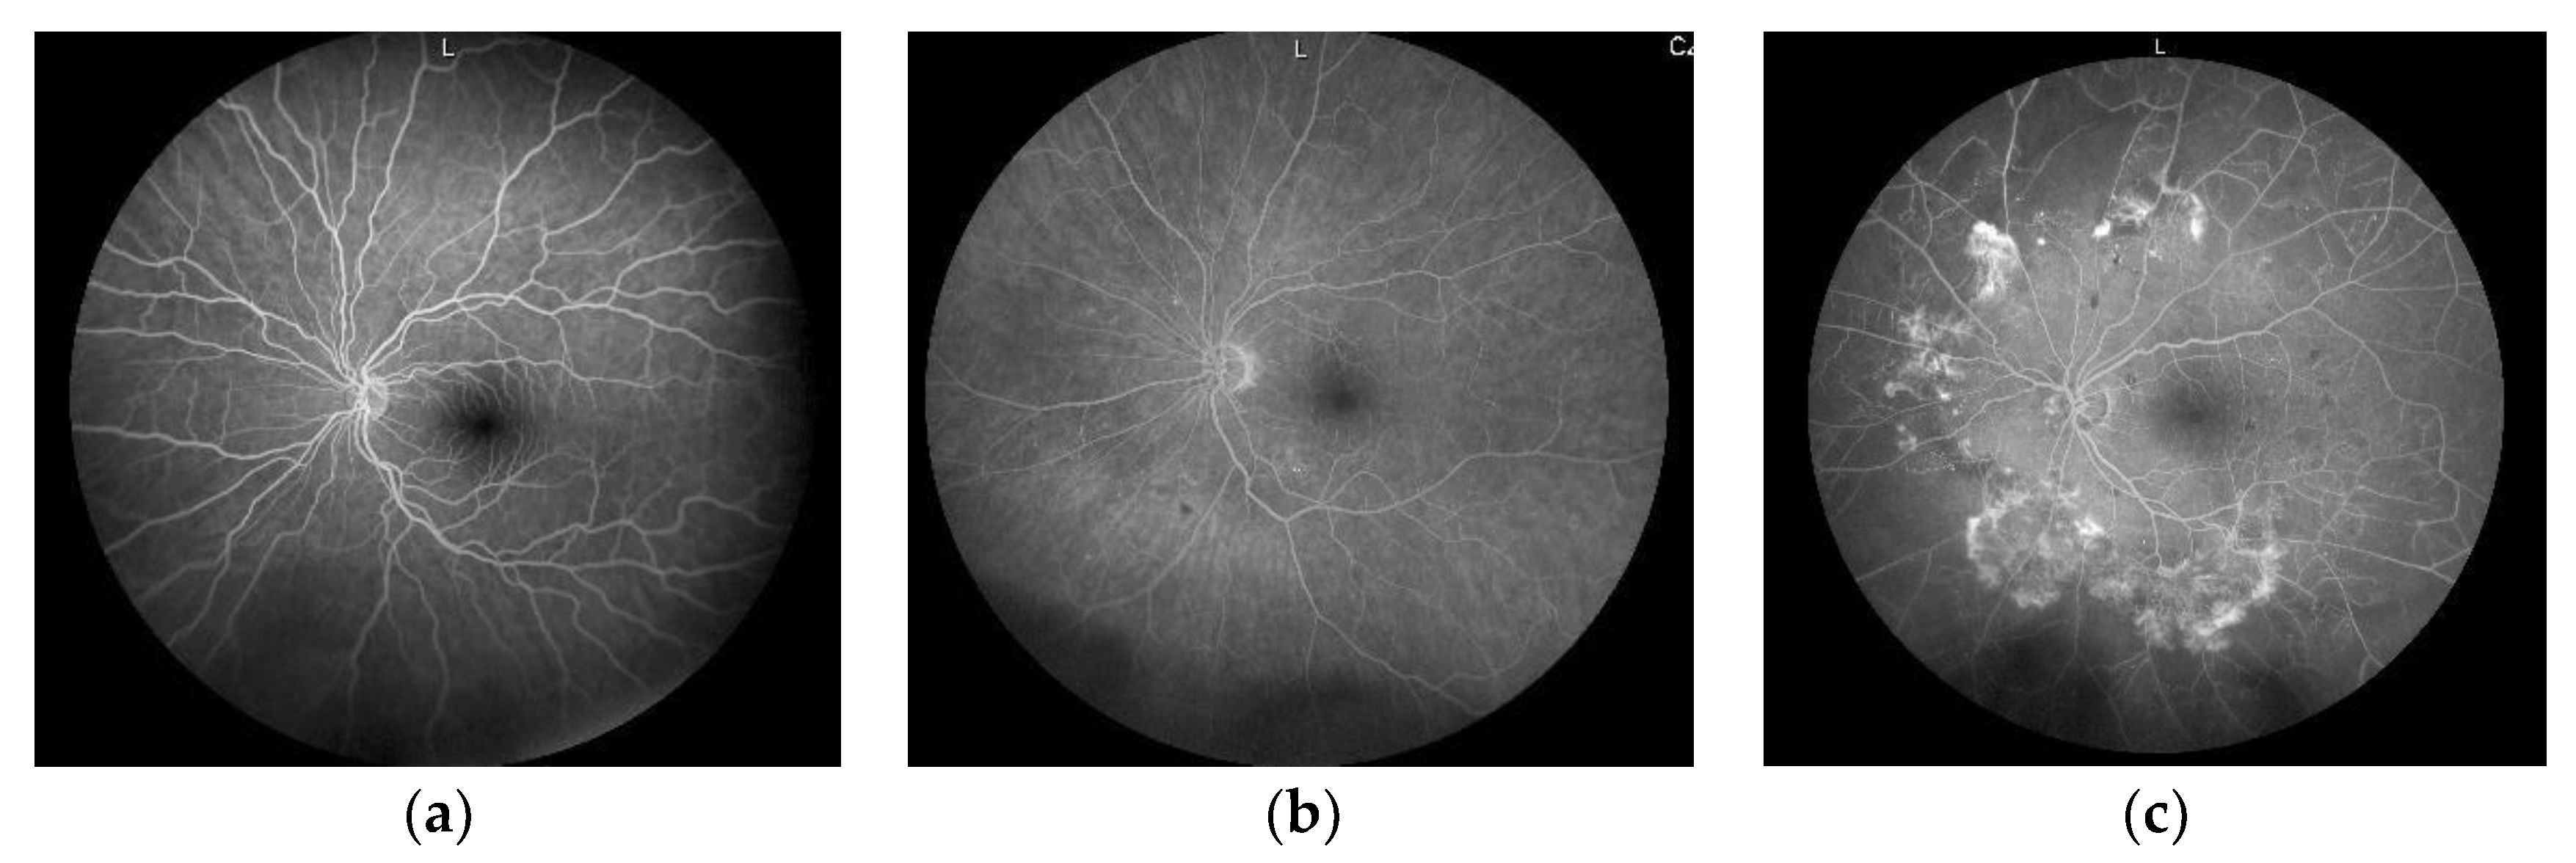

2.1.1. New Diabetic Retinopathy Dataset

- A new DR image dataset collected comprised of three classes: normal, NPDR, and PDR.